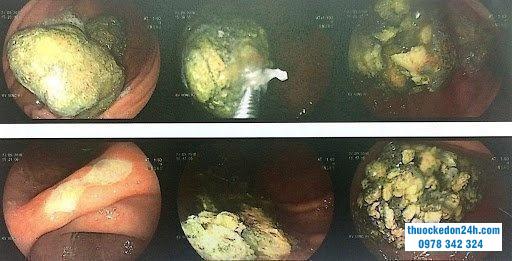

Hình ảnh gắp bã thức ăn dạ dày nhờ nội soi

Đưa ống overtube (ống nhựa cứng) qua máy soi để đảm bảo khi lấy dị vật ra không gây tổn thương ống tiêu hóa.Tiến hành nội soi dạ dày theo quy trình nội soi tiêu hóa được Bộ Y tế ban hành. Ống nội soi sẽ được đưa từ từ vào miệng, hình ảnh đầu dò sẽ truyền tới màn phép bác sĩ quan sát và đánh giá bã thức ăn dạ dày. Thòng lọng được sử dụng để cắt nhỏ từng phần cục bã thức ăn, sau đó, dùng rọ gắp dần kéo ra ngoài qua đường miệng bằng cách kéo cả dây máy nội soi ra ngoài. Đôi khi bã thức ăn rất khó cắt.